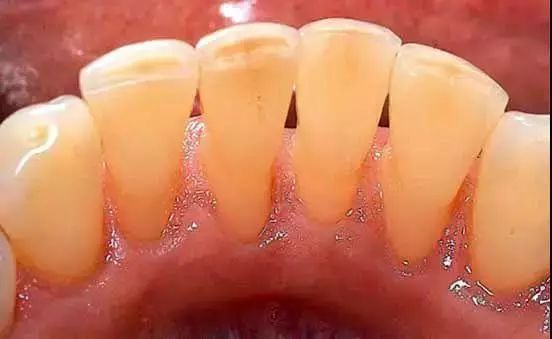

因为你看不见的地方是这样的↓↓↓

我们的口腔每天都处在水深火热中...在我们大快朵颐之后,若不注意口腔卫生,长期下来就会堆积很多黄色的,棕色的甚至黑色的脏东西,也就是牙结石。

牙结石又分为「龈上结石」和「龈下结石」,龈上结石看得见,但是龈下的就没那么容易看得见了,也很难彻底清理,会刺激牙龈,造成牙龈发炎,糜烂,出血,加上牙周炎病人牙周袋较深,易堆积细菌,最后可能会导致牙齿脱落。